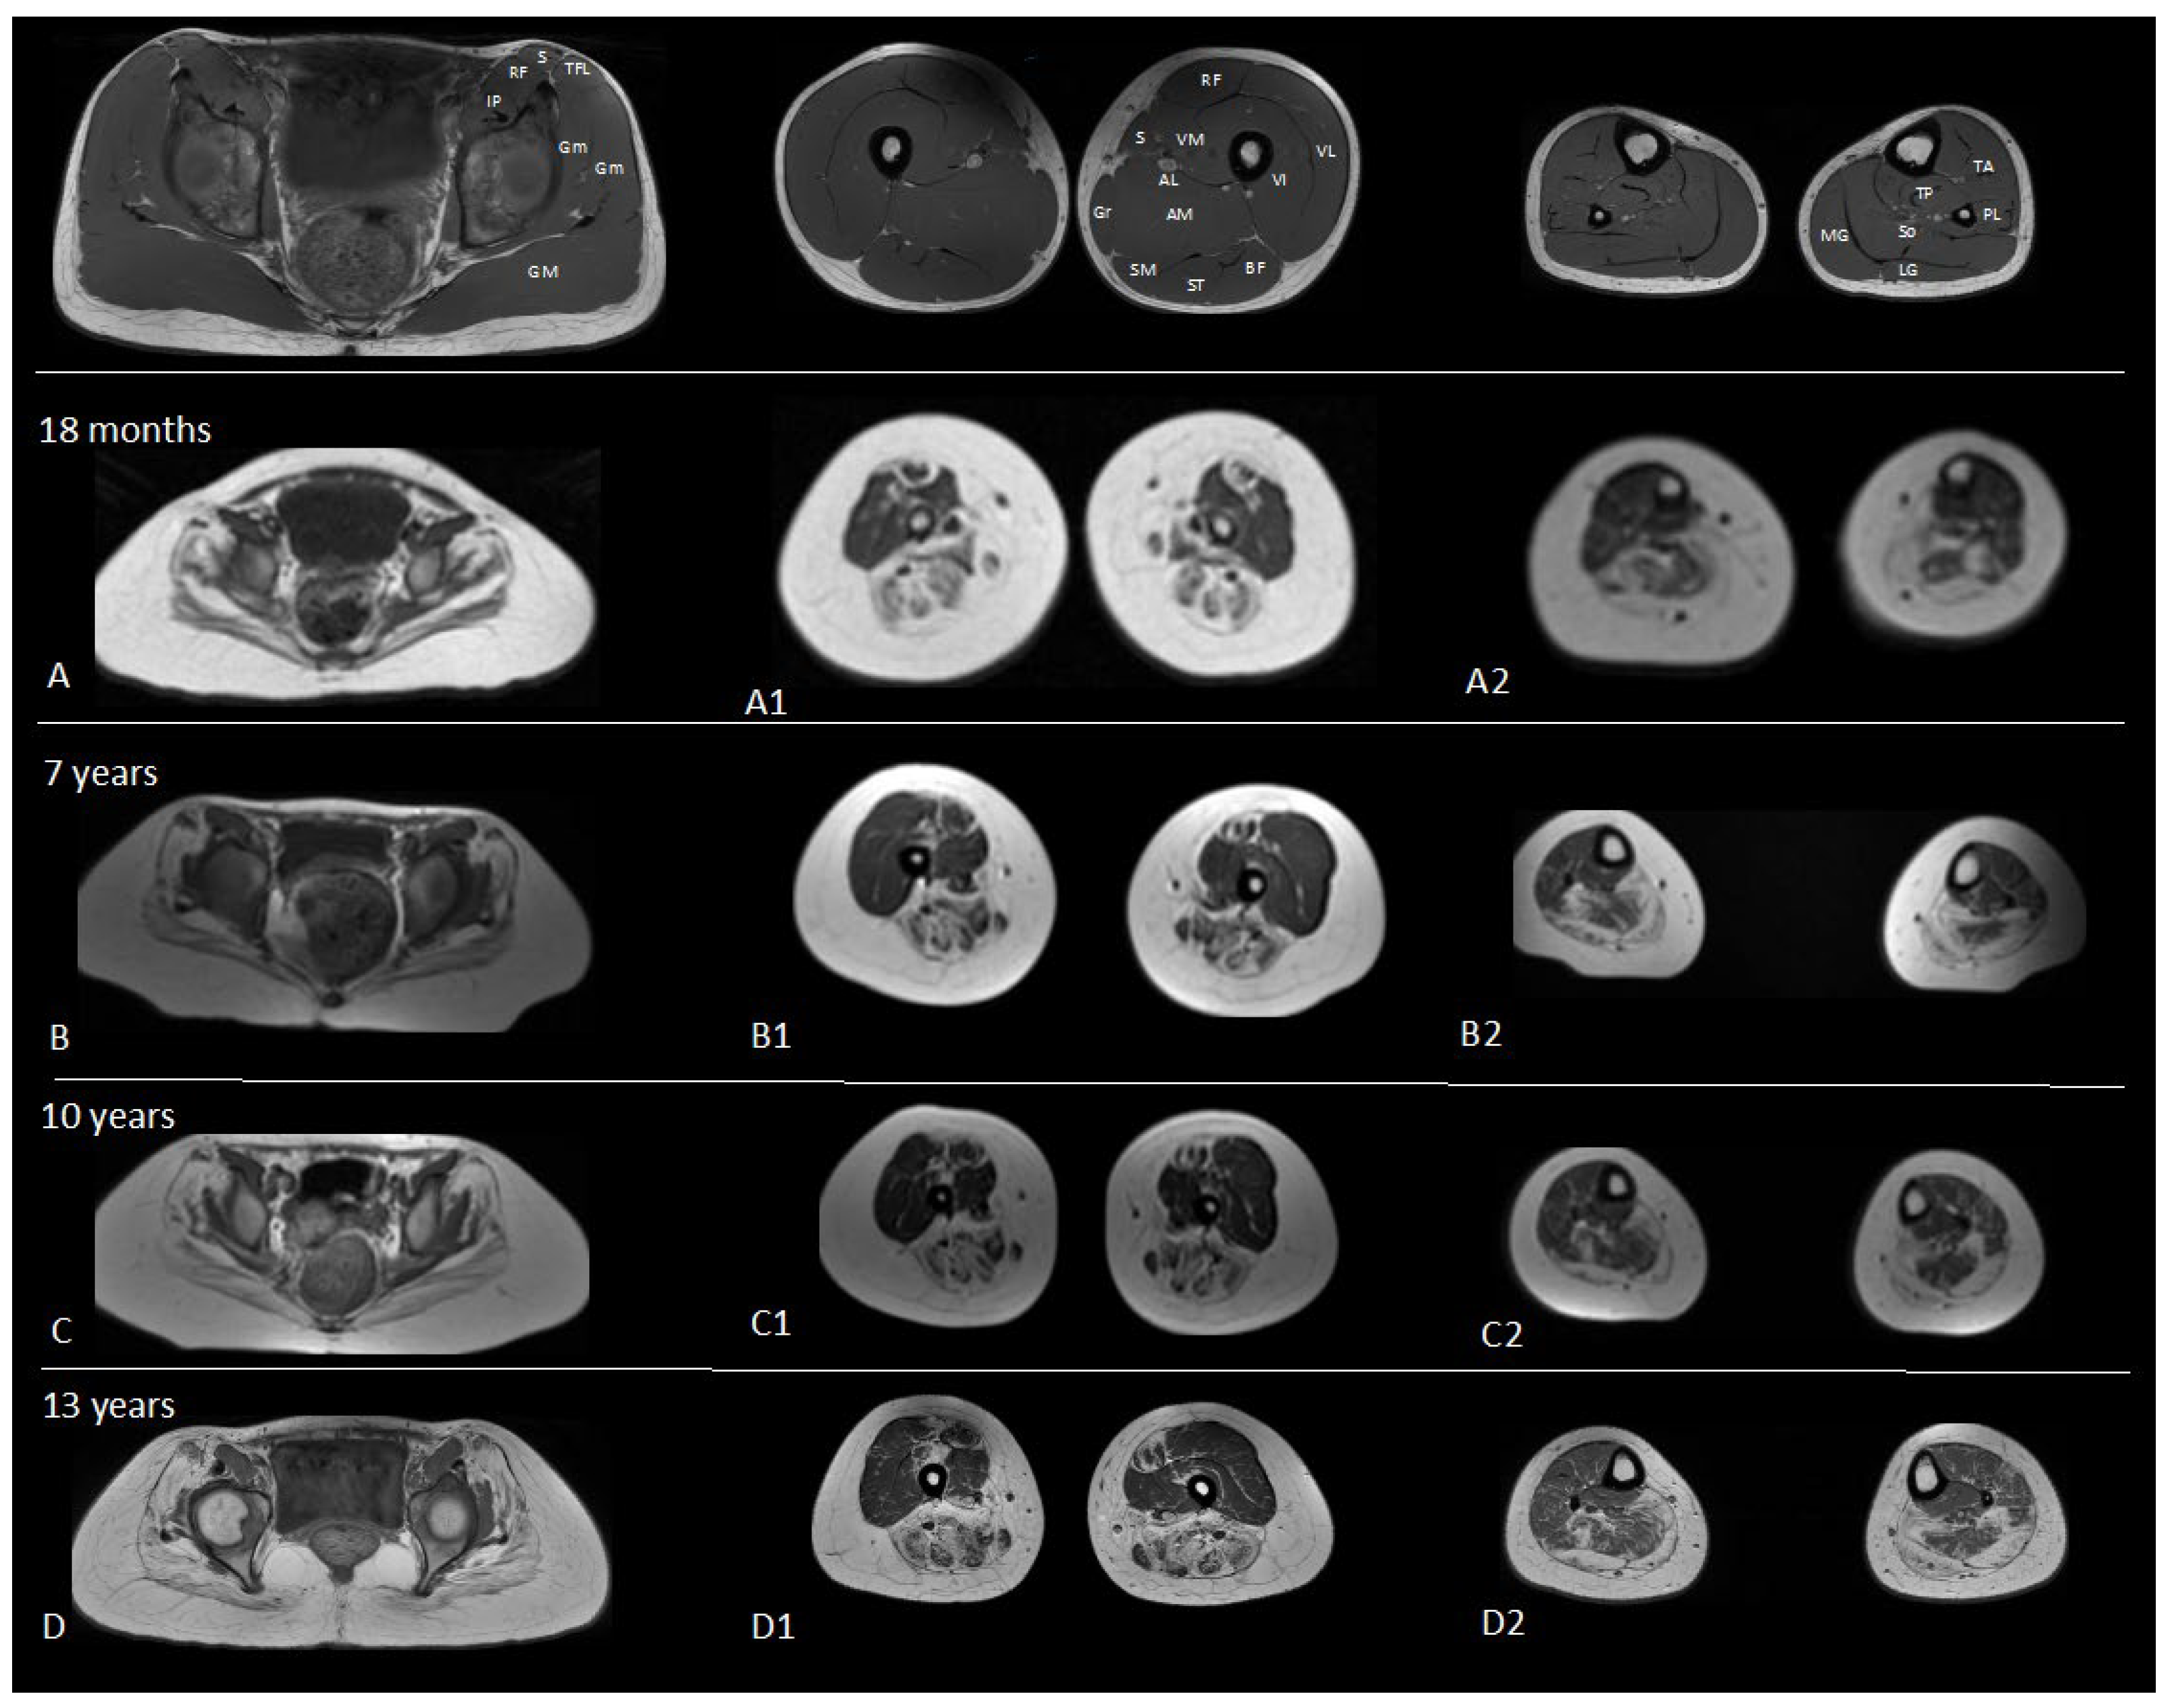

| 7 Years | 11 Years | 12 Years | 13 Years | |

|---|---|---|---|---|

| MFM total | 77.08% | 77.08% | 78.13% | 78.12% |

| D1 (standing position and transfers) | 53.84% | 51.28% | 53.80% | 51.28% |

| D2 (axial and proximal motor function) | 94.44% | 94.22% | 91.67% | 94.44% |

| D3 (distal motor function) | 90.74% | 95.23% | 100% | 100% |

| Spirometry | ||||

| FVC %/mL | 93%/1710 | 83%/2030 | 85%/2340 | |

| PEF %/L/s | 95/3460 | 80/3760 | 90/4540 |